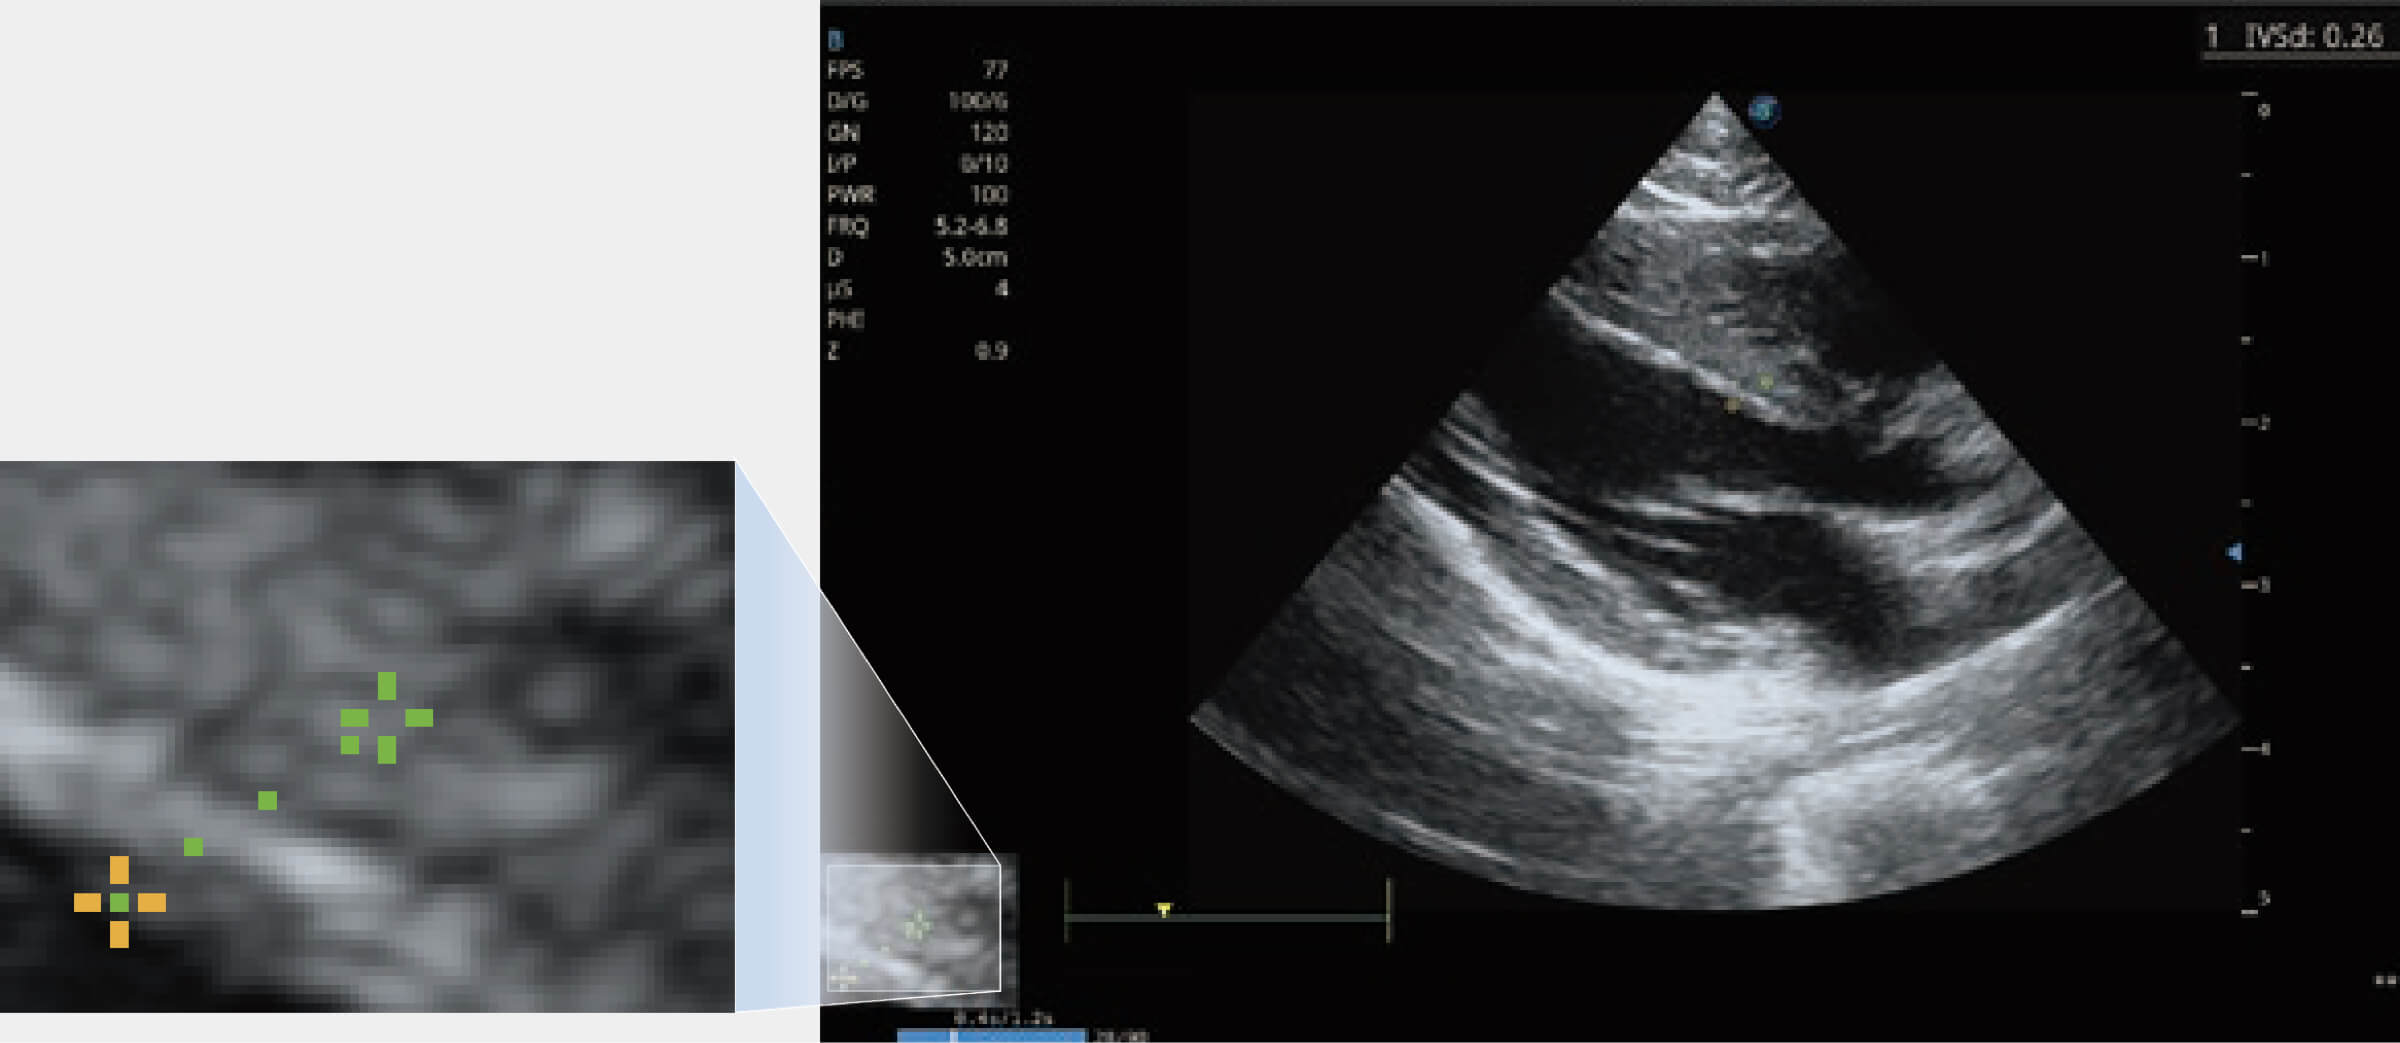

ProPet 80 配備了豐富的心臟探頭群、先進(jìn)的成像技術(shù)和專業(yè)的心臟測(cè)量工具,可幫助動(dòng)物醫(yī)生為不同體型和生理結(jié)構(gòu)的動(dòng)物提供心臟和心肌功能的全面評(píng)估。

通過(guò)心肌識(shí)別技術(shù)與二維斑點(diǎn)追蹤技術(shù)相結(jié)合,對(duì)心臟的超聲圖像進(jìn)行量化分析。計(jì)算心肌17個(gè)節(jié)段的應(yīng)變、應(yīng)變率、速度、位移等,并通過(guò)牛眼圖的形式進(jìn)行呈現(xiàn)。

通過(guò)360度任意調(diào)節(jié)3條M型取樣線,在同一心動(dòng)周期上觀察心臟不同位置的運(yùn)動(dòng)曲線,得到準(zhǔn)確的心功能測(cè)量數(shù)據(jù),有效評(píng)估心肌運(yùn)動(dòng)及左心室功能。